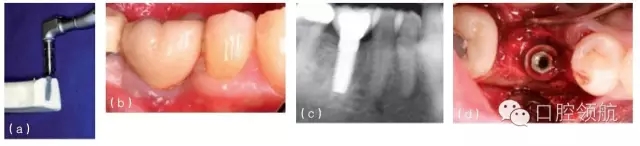

圖10.4 (a)在頜骨模型上,環(huán)鉆置于種植體上。環(huán)鉆是空心柱狀的,鉆的末端有切割螺紋。它放在種植體上,可以順著種植體邊緣周的骨組織的切線方向環(huán)行去除骨組織,從而使種植體移除造成的創(chuàng)傷減到最小。(b)種植單冠的頰面觀,種植修復(fù)后患者產(chǎn)生持續(xù)性的疼痛,且無法緩解,需要取出種植體。(c)根尖片顯示種植體正常。(d) 取出牙冠,翻瓣暴

露種植體。(e)用環(huán)形鉆取出包繞種植體的骨環(huán)。(f)環(huán)形鉆包繞種植體,環(huán)形切削達(dá)種植體全長。(g)環(huán)形鉆切削完畢,(環(huán)形鉆中心的)切除的骨組織包繞種植體,種植體周圍已被分離,只有根尖區(qū)還有骨組織與種植體相連接。將使用一種器械,置于骨環(huán)周,切斷根尖區(qū)的骨組織。(h)包含種植體在內(nèi)的骨環(huán)被取出。(i)取出后置于外科盤上,可見種植體及附著周圍薄層的骨組織。種植體植入時(shí)曾植骨,種植體周可見殘留的顆粒狀的骨移植材料。(j)種植體移除后,去骨創(chuàng)面的牙合面觀。(k)將骨移植材料(同種異體骨與異種骨移植材料混合)放置在去骨創(chuàng)面中。(l)放上屏障膜,用釘固定。